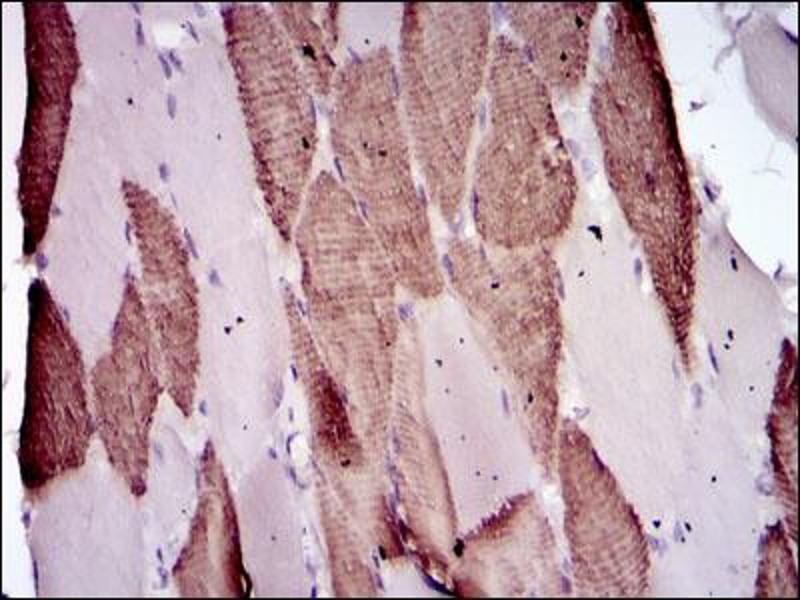

Approved: ELISA (1:10000), Flo (1:200 - 1:400), IF (1:200 - 1:1000), IHC, IHC-P (1:200 - 1:1000), WB (1:100 - 1:500)